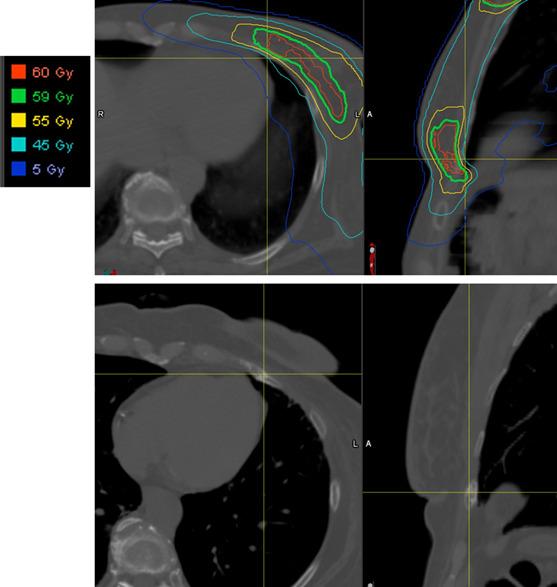

From a prospective database, we identified 225 patients treated with proton therapy between 2012 and 2020 (223 women; 2 men). Clinical and dosimetric data were extracted, the cumulative incidence method assessed rib fracture rate, and Fine-Gray tests assessed prognostic significance of select variables. In-field rib fracture was defined as a fracture that occurred in a rib located within the 10% isodose line. Out-of-field rib fracture was defined as a fracture occurring in a rib location outside of the 10% isodose line.

Of the patients, 74% had left-sided breast cancer; 5%, bilateral; and 21%, right-sided. Dual-energy x-ray absorptiometry scans showed normality in 20%, osteopenia in 34%, and osteoporosis in 6% (test not performed in 40%). Additionally, 57% received an aromatase inhibitor. Target volumes were breast ± internal mammary nodes (IMNs) (16%), breast and comprehensive regional lymphatics (32%), chest wall ± IMNs (1%), and chest wall/comprehensive regional lymphatics (51%). Passive-scattered proton therapy was used for 41% of patients, 58% underwent pencil-beam scanning (PBS), and 1% underwent a combination (passive scattering/PBS), with 85% of patients receiving a boost. Median follow-up was 3.1 years, with 97% having >12-month follow-up. The 3-year cumulative in-field rib fracture incidence was 3.7%. Eight patients developed in-field rib fractures (1 symptomatic, 7 imaging identified) for a 0.4% symptomatic rib fracture rate. Median time from radiation completion to rib fracture identification was 1.8 years (fractures were identified within 2.2 years for 7 of 8 patients). No variables were associated with rib fracture on univariate analysis. Three fractures developed outside the radiation field (0.9% cumulative incidence of out-of-field rib fracture).